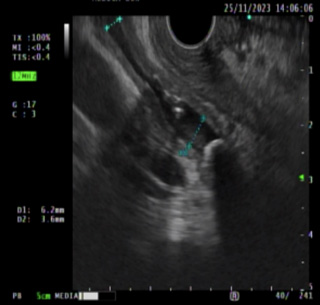

use 03

Imagen 3. Biopsia guiada con aguja de tumor de la pared del estómago